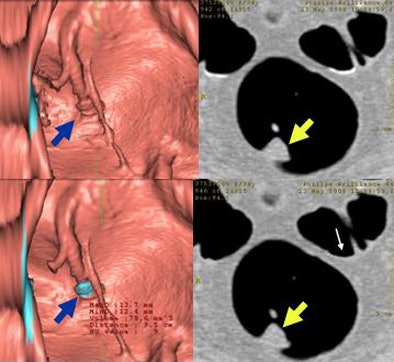

![]() |

| Without electronic cleansing, a 10-mm polyp was missed by CAD due to its flat morphology (top row above). After electronic cleansing was applied, CAD successfully detected this polyp (bottom row above). The lesion was confirmed as a well-differentiated adenocarcinoma on pathologic examination (below). |